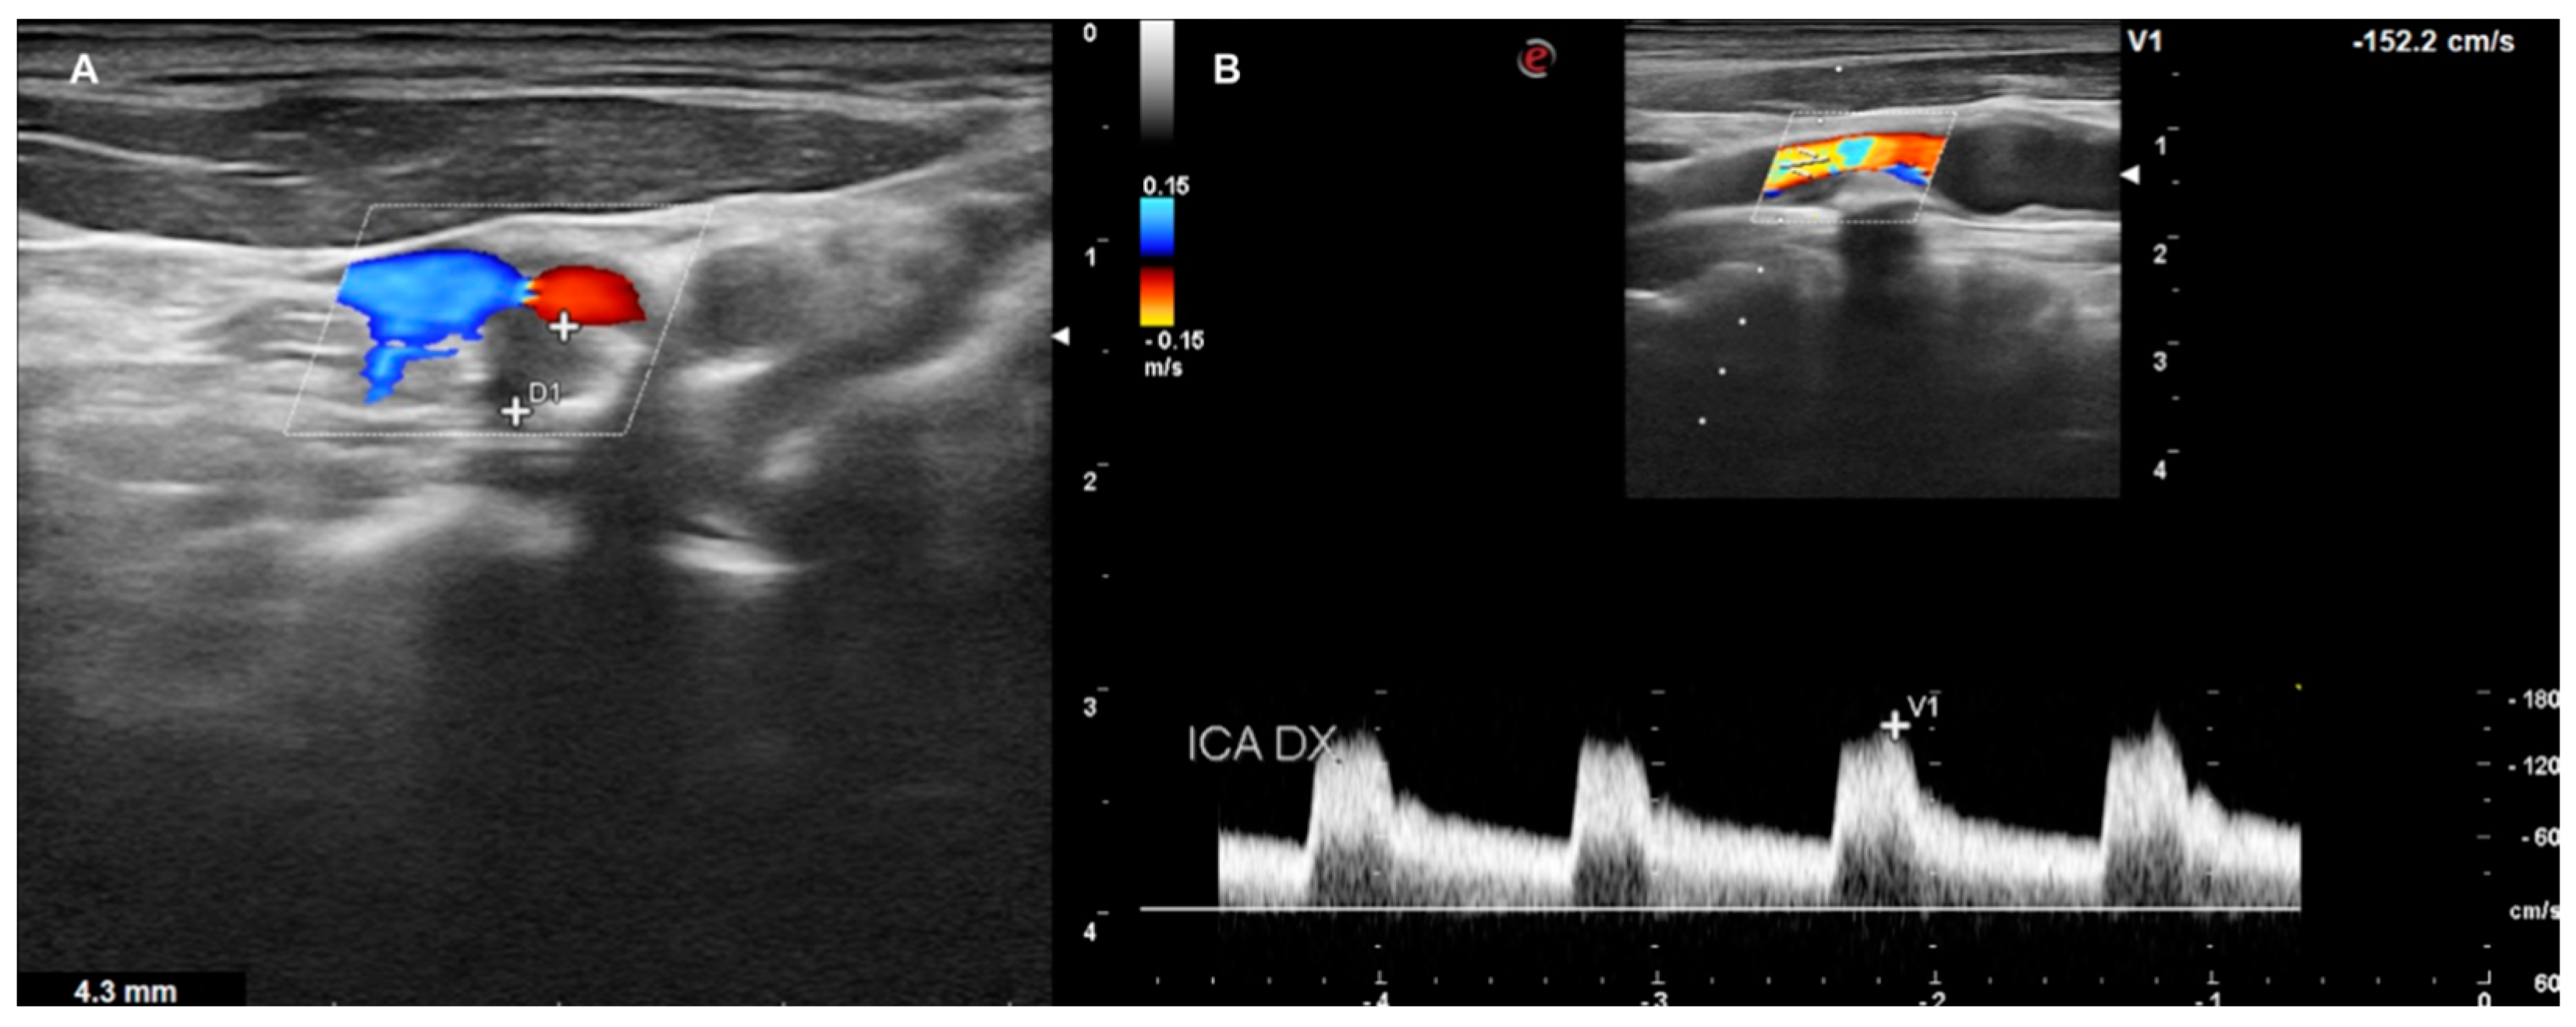

- HIGH GRADE: Patients presenting a carotid plaque over 30% and further divided in the first step (under 50% of stenosis), the second step (stenosis between 50% and 70%), the third step (above 70%). All patients in this group underwent cardiologic assessment, with echocardiography, electrocardiogram, and DUS of peripheral arteries (Figure 7).

Figure 7. DUS images showing plaque in CCA—HIGH GRADE (A), and its relative flow (B).